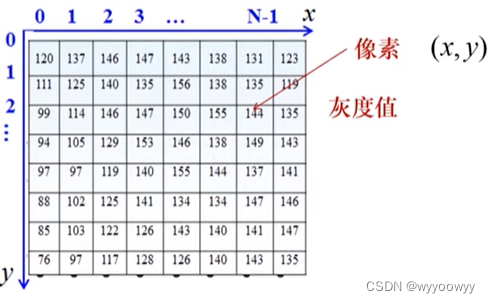

图像用数组表示:(i,j,k,t均为整数)

2D image:f(i,j)

5、数字图像三要素:

Pixel(picture elements)–像素

Gray level --灰度值

Coordinates–坐标

灰度值:一般表示在0-255的范围内

因为通常使用一个字节表示一个像素,(2^8=256)所以灰阶表示在0-255的范围